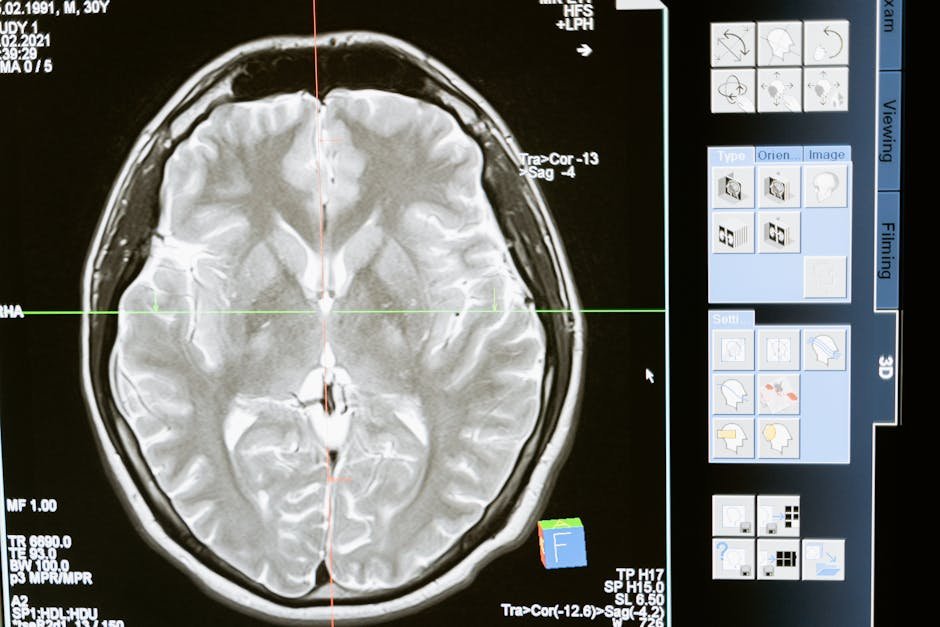

They took a knife to the corpus callosum. That’s the nerve bridge connecting your brain’s right and left sides. Cats and monkeys? Totally fine after this. So, why not people? Carl Lashley, a psychologist dude, even thought this bridge was just hanging out, basically just holding the brain together.

For ages, people just thought the corpus callosum was, like, a dumb wire. Nope. And another thing: this thing’s intricate, packed with over 200 million little brain connections, zipping about a billion bits of info every single second. A super important info superhighway.

Our whole nervous system is, like, criss-crossed. Right brain handles the left body, left brain handles the right. You get it. Even stuff we see – visuals from our eyes – crosses over at this spot called the optic chiasm. Sever that bridge? Boom. Massive communication breakdown. Major brain mix-up.

A: It’s the main nerve cable deep inside your head, linking the brain’s left and right sides. Has, like, 200 million connections. It’s a data superhighway, quickly sharing info. No callosum? Your brain halves are on their own.